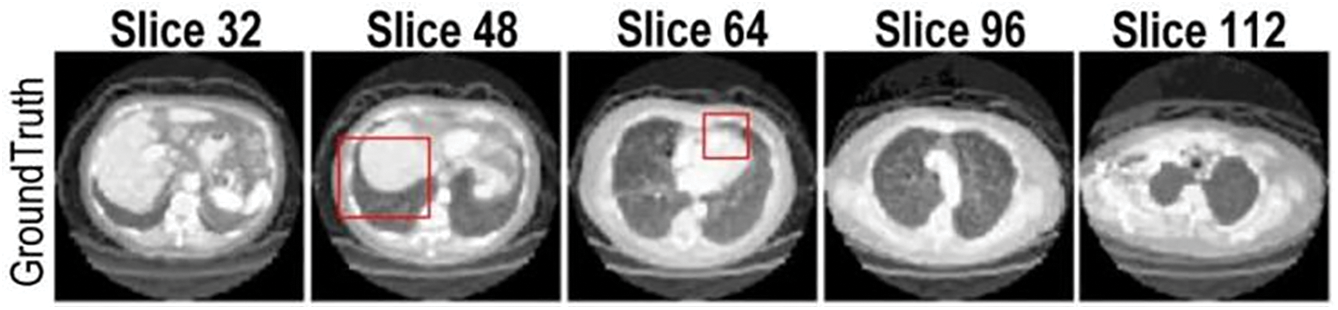

The experimental results in this study are analyzed from both quantitative and qualitative perspectives. The quantitative analysis uses three evaluation indexes, SSIM, PSNR, and MAE, to evaluate and average the test sets in the data set. The qualitative analysis uses a test sample to show reasoning results for different network structures. The test sample inputs for all qualitative analyses in this section are Cor and Sag, as shown in Fig. 12.

Figure 12: Qualitative analysis test samples Cor and Sag

In terms of qualitative evaluation, the reasoning results of the four networks on the test samples are shown in Fig. 17. The experimental results show axial (horizontal) slices extracted from the reconstructed 3D volume at the same anatomical level as the source CT.

Figure 17: Qualitative evaluation of ablation experiments

The reconstruction result of SingleViewNet has obvious unreasonableness in the chest edge contour. Based on it, AvgFusionNet adds another sag as input, which improves the chest contour information, but there are still obvious deficiencies in the lung contour. After adding the adaptive fusion module to ConfFusionNet and AdapFusionNet, there are obvious improvements in both chest contour and lung contour reconstruction. The improvement of the reconstruction effect by the adaptive fusion module is very obvious in qualitative evaluation.

The edges of ConfFusionNet are very clear, and the grayscale is relatively consistent within the same tissue, but the noise is obvious. The contour of AdapFusionNet is relatively clear, but the grayscale distribution within the same tissue is somewhat uneven. Although the contour of this fusion method is not as clear as ConfFusionNet, it will not bring additional noise at the same time. In summary, AdapFusionNet is significantly better than SingleViewNet and AvgFusionNet in qualitative evaluation and has a slight advantage in quantitative evaluation.